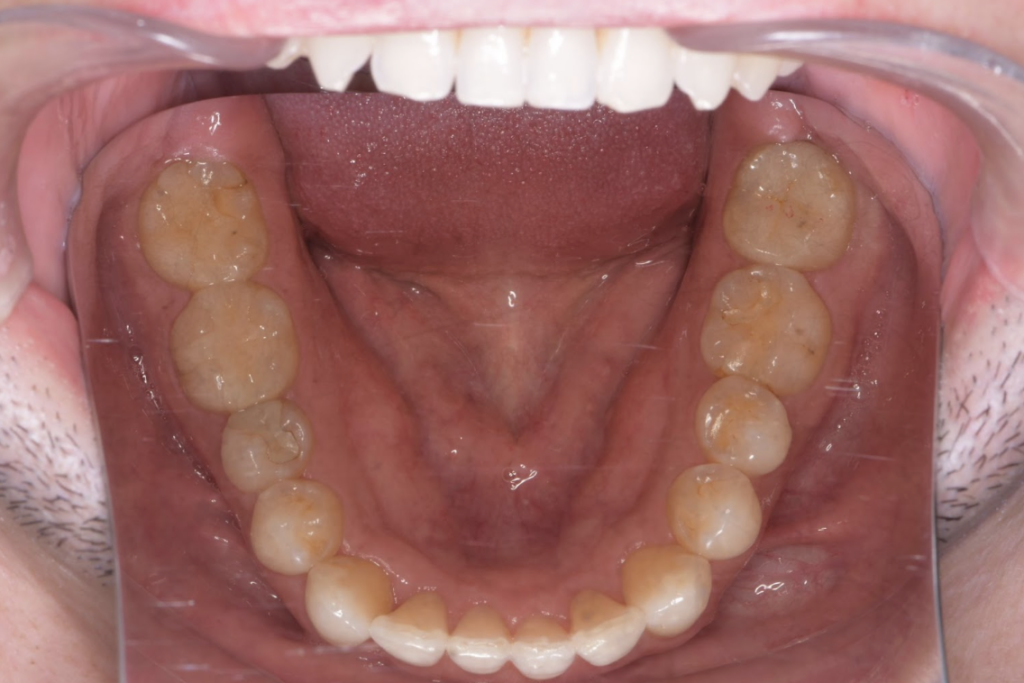

以下は症例写真です。

長年使用していた金属の詰め物を、生体親和性の高いセラミック素材に置き換えました。

天然歯のような透明感が生まれ、金属アレルギーの不安も解消されています。

<術後の写真>